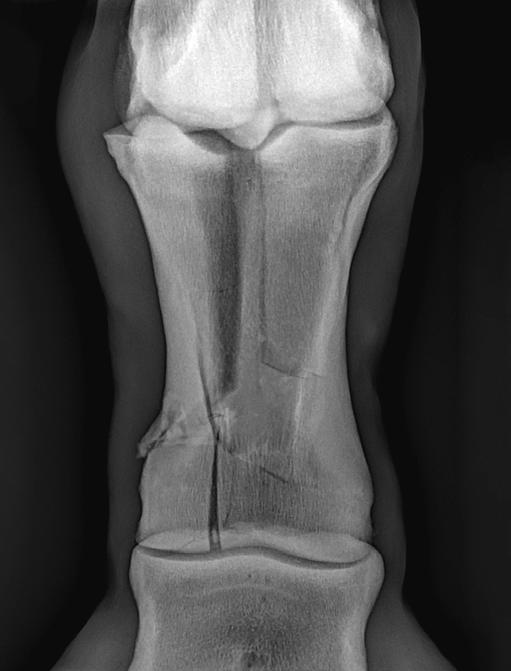

Tendons and ligaments are distinct but closely related tissues that have unique and important roles in musculoskeletal function and musculoskeletal disease. Tendons and ligaments are dense, fibrous connective tissues that connect muscle to bone or bone to bone, respectively. These tissues transmit mechanical forces to stabilise the skeleton and allow body movement. Tendons and ligaments consist mainly of collagen type I as well as small amounts of collagen III, IV, V, and VI. There are also various proteoglycans in tendons and ligaments that both organise and lubricate collagen fibre bundles. The elasticity of tendons and ligaments is due to the large amount of type I collagen. During locomotion, the tendon decreases energy cost to the horse by acting as a spring to store and release energy while stretching and recoiling in the stance and swing phases of each stride. Tendons and ligaments have blood vessels and nerves that allow the homeostasis and response to injury.

Tenocytes are tightly regulated by a series of growth factors and transcription factors that allow the synthesis, maintenance, and the degradation of the tendon extracellular matrix. Tendons are elastic, but tearing may occur if there is excessive loading on the tendon and the repair of collagen is a slow process. In addition, tendons have crimp morphology where the tendons buckle in a state of relaxation and act as shock absorbers. Unbuckling of the tendon occurs during loading. This crimp morphology may be disturbed if an injury occurs and also is reduced in older horses.

Due to the variation of activity of tenocytes in foals and young horses, it has been observed that both a lack of exercise and excess of exercise can impair tendon make-up and subsequent functionality. With the current data and research that has been gathered, it can be concluded that if horses take advantage of spontaneous exercise when in the paddocks (which they often do), the developing tendons may benefit and be at a lower risk of injury when racing training starts.

Conclusion

It is clear that further research is needed in order to ascertain the optimal amount and type of exercise that is needed in order to provide a strong musculoskeletal system and functional performance. However, it has been shown that prescribed exercise during the growth of the horse can increase the longevity of the horse’s health and performance. It has been observed that confinement and the lack of loading can result in weaker tissues and the loss of function of bone, tendons, ligaments and articular cartilage. However, it must also be recognised that medical attempts to alleviate pain so that a horse can continue to train through an injury can greatly increase tissue damage which is detrimental to the horse’s health and career. It is far more beneficial to provide an adequate amount of time for the injury to heal, thus, putting the horse’s health and wellbeing as a top priority.

Due to the variation of activity of tenocytes in young horses, both a lack of exercise and excess of exercise can impair tendon make-up. The horse has no muscle below the knee and hock therefore relies on tendons and ligaments which transmit forces to stabilise the skeleton and allow body movement. PHOTOGRAPHY: ADOBE STOCK, DAVID BETTS PHOTOGRAPHY, GALOPPFOTO.DE, ECLIPSE SPORTSWIRE, SHUTTERSTOCK